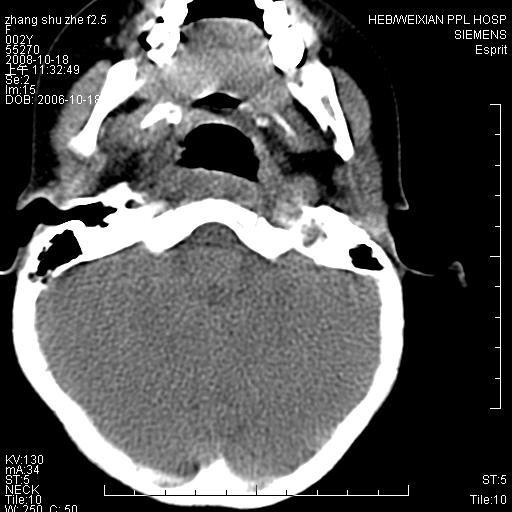

以下是引用dyqct在2009-2-10 21:04:00的发言:[br]年龄?性别?有发烧吗?[br]鼻咽部、口咽部、喉咽部及颈椎前间隙广泛肿厚,明显占位效应并致相应组织变形。ct值22-28hu。[br]考虑:1、颈前脓肿可能性大;[br] 2、建议增强或治疗后复查。

以下是引用jiangjing在2009-2-11 11:37:00的发言:[br]急性病程,鼻咽部、口咽部、喉咽部及颈椎前间隙广泛肿厚,明显占位效应并致相应组织变形.考虑颈部感染性病变(脓肿?);建议行进一步检查。